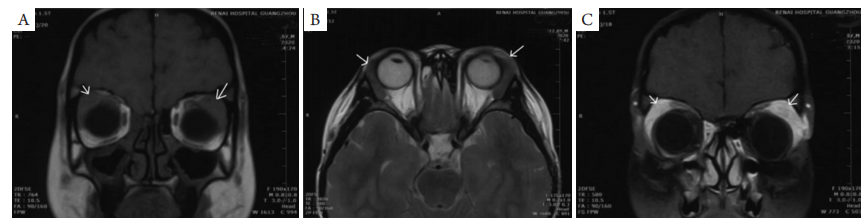

图2 患者术前眼眶MRI示双侧泪腺肿物(箭头),与周边组织边界欠清,大小约为1.1 cm×2.7 cm

Figure 2 MRI before surgery indicated that the mass has involved bilateral lacrimal glands with unclear boundary (arrows), measuring about 1.1 cm × 2.7 cm

(A)在T1图上显示中等强度信号;(B)在T2图上显示稍高强度信号;(C)增强扫描病灶较明显均匀强化。

The mass shows (A) intermediate signal intensity on T1, (B) slightly hyperintense on T2 and (C) significant enhancement on gadolinium enhanced T1-weighted MRI.

然而,并不是所有KD的IgE水平均升高,如Dokania等[10]报道了1例没有外周血嗜酸性粒细胞水平升高,而最终通过病理活检确诊KD。在MRI影像学检查上,KD的肿块在T1图像上的信号强度可高可低十分多样,T2呈高信号[11]。本病例左侧泪腺MRI示T1和T2中等信号强度,增强T1信号明显且均匀强化。特别的是,本病例MRI结果显示患者还伴随轻度鼻窦炎,而KD与鼻窦炎的关联非常罕见。Carrera和Silkiss[12]曾报道1例并发性慢性鼻窦炎的KD,有趣的是这个病例也累及双侧泪腺,确切原因尚不清楚,但可能与自身免疫相关。累及双侧泪腺的KD与并发性慢性鼻窦炎病因及关系有待进一步研究。